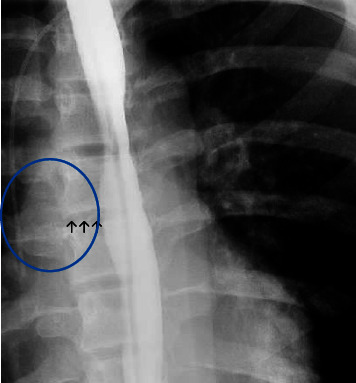

Streptococcus intermedius is an inhabitant of the oral cavity and gastrointestinal tract, known to cause deep-seated abscesses. Thereby, we present a previously healthy adolescent with esophageal perforation (EP) and secondary mediastinal and brain abscesses due to Streptococcus intermedius. EP is a potentially life-threatening condition that requires a prompt diagnosis.